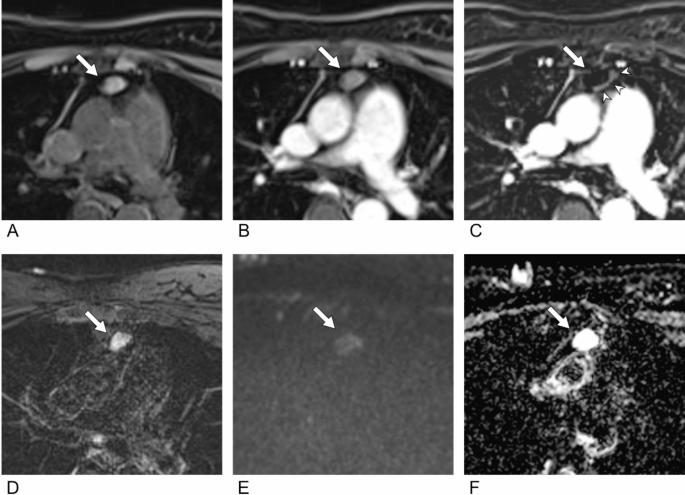

In Institution A, for the three-category scale, the inter-reader agreement was the highest (κ = 0.53) in Session 4, in which pre- and post-contrast CT scans were included, followed by Session 3 (κ = 0.51); however, no statistically significant difference in inter-reader agreement was observed (p = 0.699) (Table 2, Supplementary Table 3). The inter-reader agreement was the lowest (κ = 0.42) in Session 2, which included the subtracted image without DWI and the ADC. The majority of discrepancies were attributed to suspicious eccentric wall thickening on the subtracted image (Fig. 2). For the two-category scale, the highest inter-reader agreement (κ = 0.57) was observed in Session 3, in which all available MR sequences were provided (Fig. 3), followed by Session 1 (κ = 0.53), in which only fundamental MR sequences were provided. No significant differences in inter-reader agreement were observed between sessions, even with the addition of CT (all, p-values > 0.05).

Example of discordance caused by a subtracted image in a 53-year-old woman. (A) A T2WI shows an 18-mm nodule with internal T2 hyperintensity in the anterior mediastinum (arrow). (B) The nodule showed hyperintensity on pre-contrast T1WIs (C) but did not show internal enhancement on post-contrast T1WIs. However, (D) the subtracted image showed subtle hyperintensity mimicking solid enhancement. (E) The lesion shows subtle high intensity on DWI, (F) but the corresponding ADC value was high, indicating that diffusion restriction was not present. Therefore, all readers diagnosed the lesion as definite cyst in Session 1 (T2WI + pre- and post-contrast T1WI + DWI/ADC map). However, in Session 2 (T2WI + pre- and post-contrast T1WI + subtracted image), two readers (Readers 1 and 3) changed the diagnosis based on the enhancement being suspicious (indeterminate) or solid enhancement being real (definite non-cyst), whereas the others (Readers 2 and 4) consistently diagnosed the lesion as a definite cyst based on the enhancement on the subtracted image being a misregistration artifact.